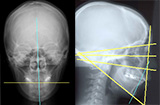

2.頭部X線規格写真

顔の骨格と正中線の歪みを検証

- セファログラムというX線規格写真で矯正治療前と矯正治療終了後の確認を行い、変化を把握します。 上下顎の大きさとそのズレ、顎の形、歯の傾斜角、口元のバランスなどを検証します。